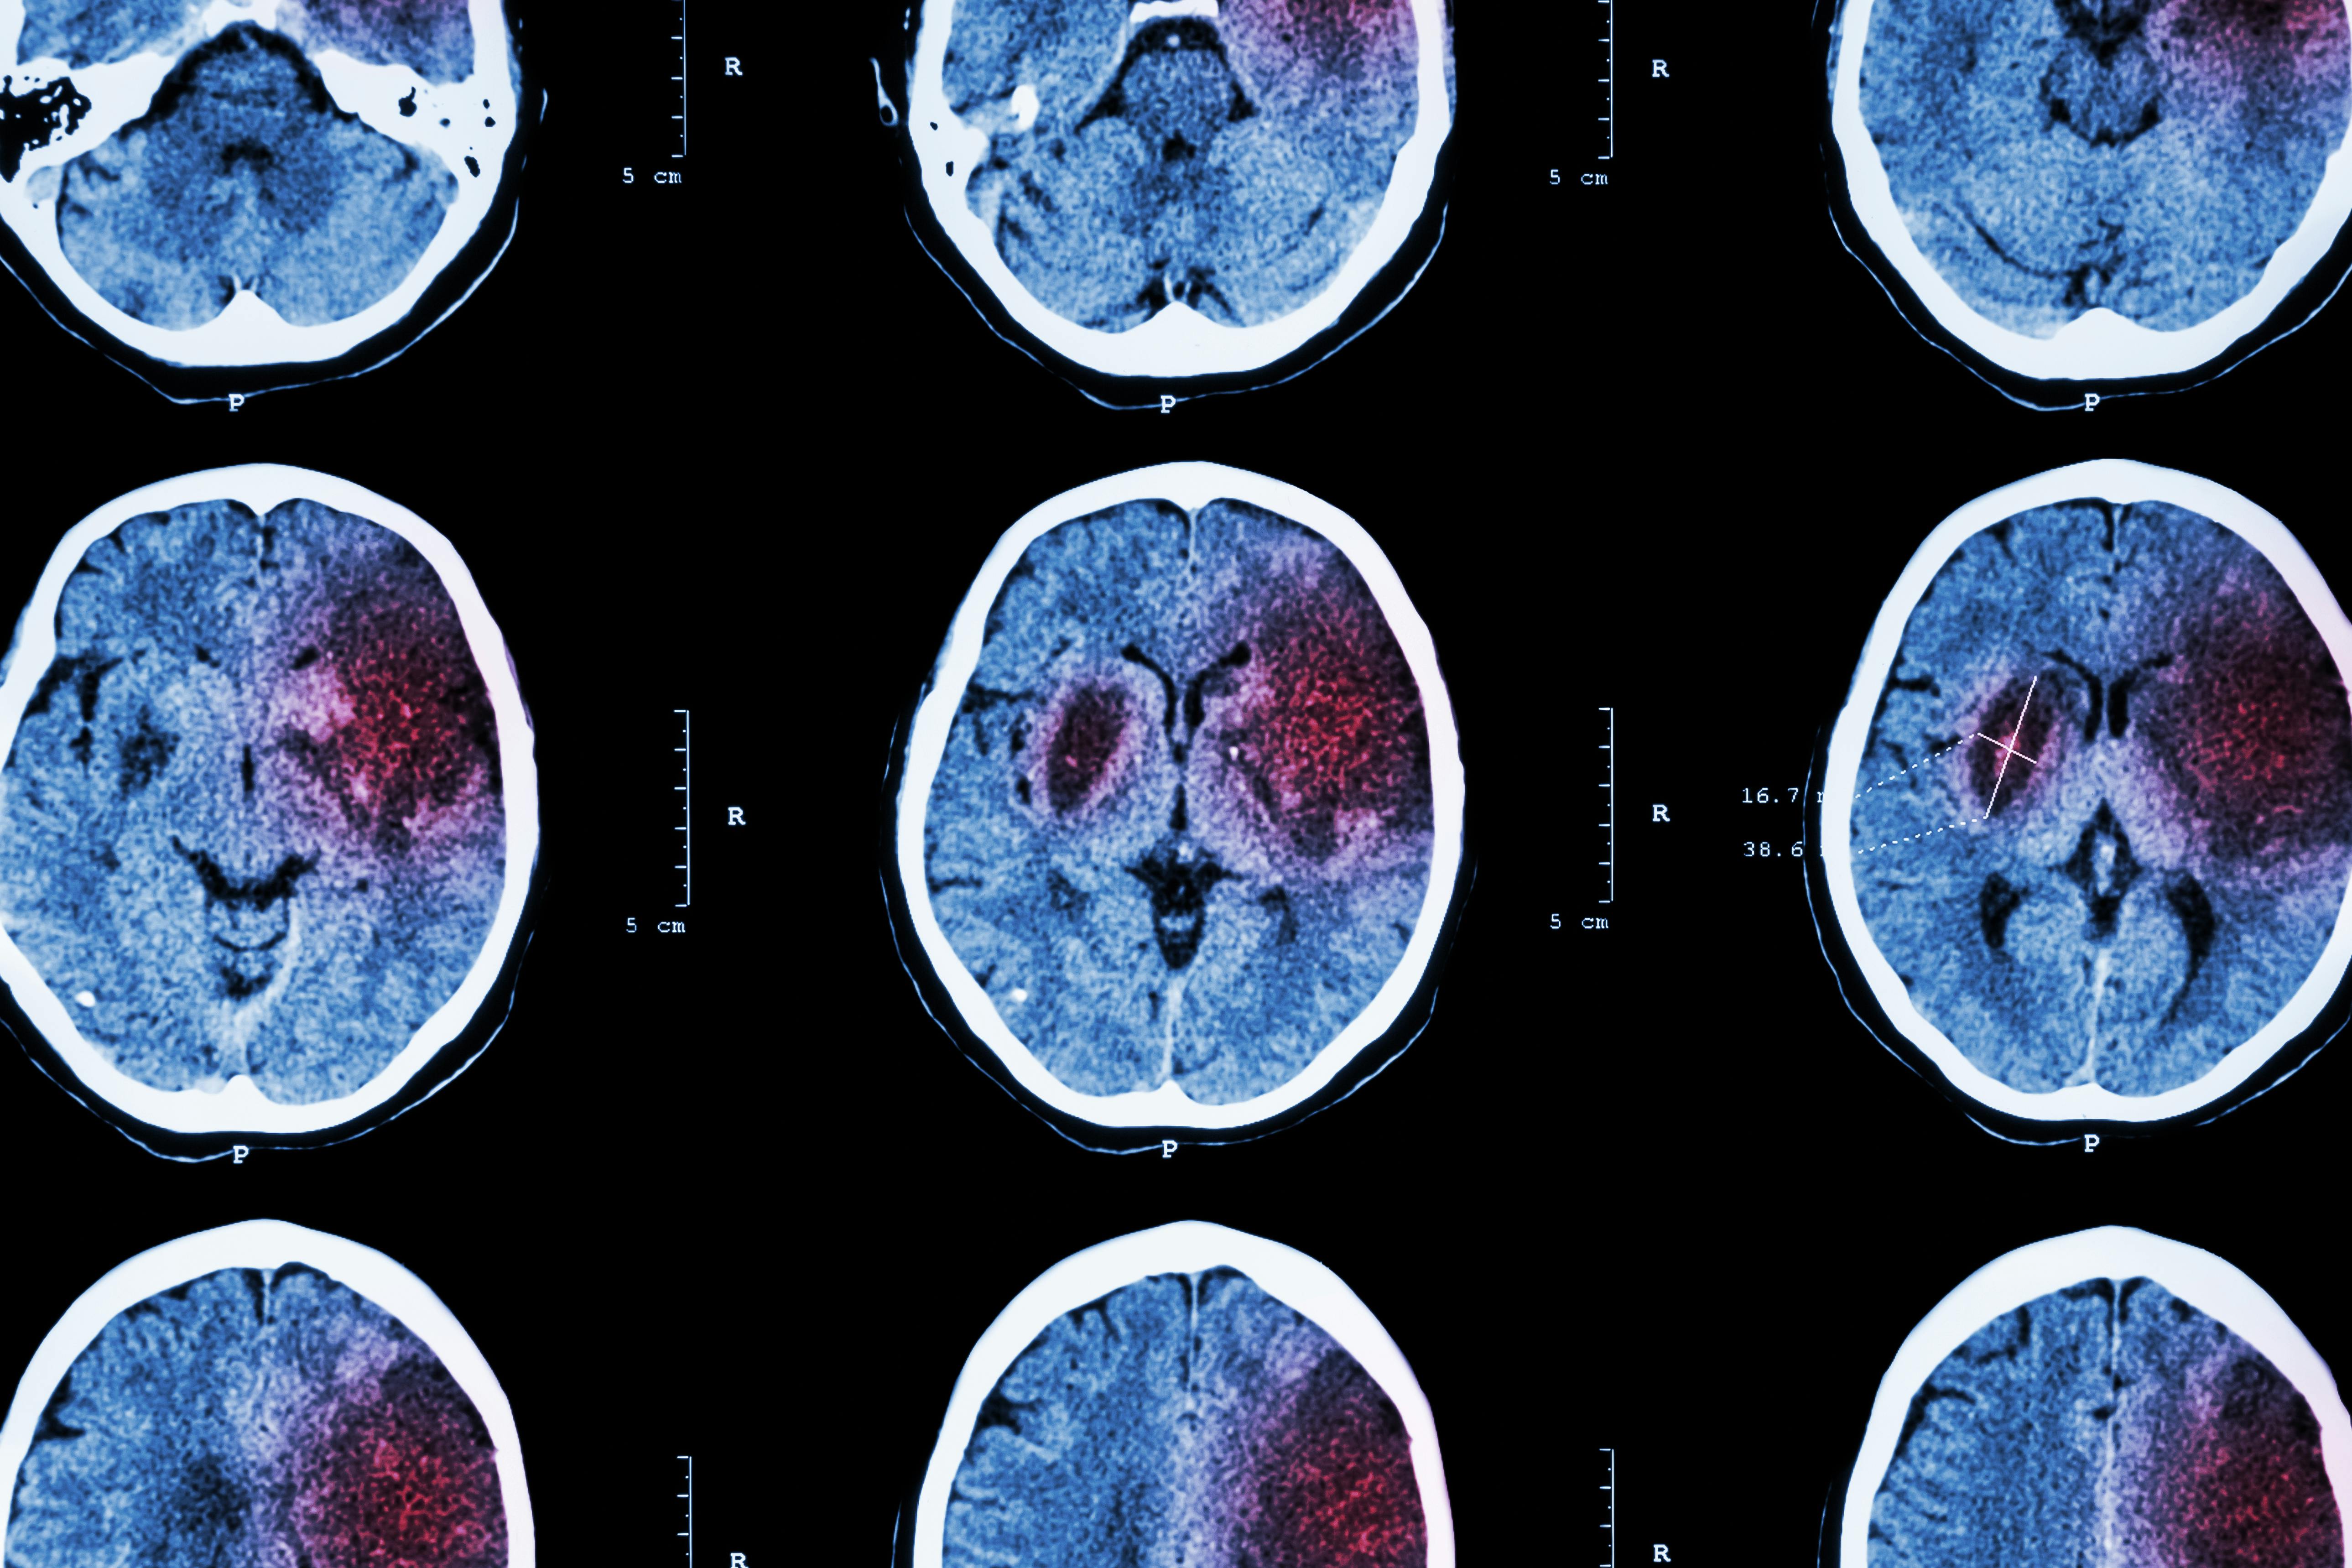

Uric Acid Shows Promise in Treating Ischemic Stroke, Study Shows

Ischemic stroke “occurs when a blood clot or other blockage in an artery cuts off blood supply to the brain. Strokes are treated with medications or surgery aimed to break up clots and restore blood flow to affected brain areas. These therapies are highly effective, but not all people fully recover. Using additional treatments that protect brain tissue from damage, either immediately before or during clot removal, could boost the effects of standard treatments and greatly improve recovery in patients.”